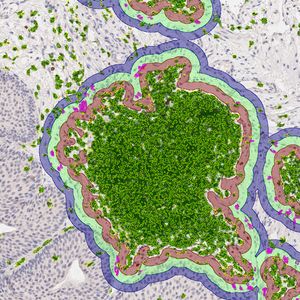

FEB 09, 2024CancerHistopathology describes the process of examining pieces of tissue using a microscope. Light microscopic (LM) exam ...